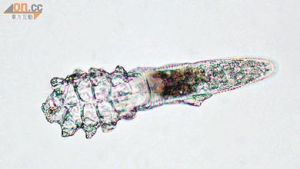

毛囊蠕形蟎寄生於人體的頭皮、乳頭、面部、胸、臂等處的毛囊內。以其顎體朝向毛囊底部各足緊貼毛囊上皮,一個毛囊內常有 6 個以上蟲體群居,多時可達18個。成蟲和若蟲多分布於毛囊皮脂腺管的上端,卵和幼蟲以及部分成蟲在毛囊皮脂腺管內和皮脂腺內。皮脂蠕形蟎常單個寄生在皮脂腺和毛囊中,致病力較低。它們刺吸人體細胞和皮脂腺分泌物,少數取吸角蛋白。由於嗜習吸食人體皮脂,所以在皮脂腺豐富的顏面部感染率高,尤以鼻尖最高,為69.7%、鼻翼為68.3%,頦56.8%外耳道38.5%。它們的寄生引起毛囊蟲皮炎,在鼻尖、鼻翼兩側出現皮膚瀰漫性潮紅、充血,並有散在集簇的針尖大至粟粒大的紅色丘疹,即形成酒糟鼻,嚴重時可累及額、頦、頰及眼周皮膚,以至軀幹、上肢,出現散在性紅色斑丘疹,在嬰兒背部濕疹狀紅斑疹。臨床表現

就是從鼻子或比較油性的部位取一點油脂分泌,放在顯微鏡下觀察,因為顯微鏡觀察直觀科學,但是也有一定的局限性,可能單次檢測是看不到蟎蟲,要多次重複檢測。

蟎蟲是一種寄生蟲不是細菌,所以要求檢測的操作人員使用顯微鏡時,物鏡10倍、目鏡10倍就可以了,不需要高倍鏡。滴劑就用一般的植物油或花生油就可以了。